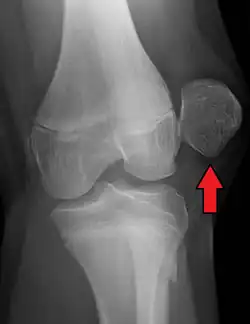

X-ray and MRI after luxation of the patella. There is a fragment and bone bruise at the medial surface of the patella and in the corresponding surface of the lateral condyle of the femur. The medial retinaculum of the patella is disrupted.